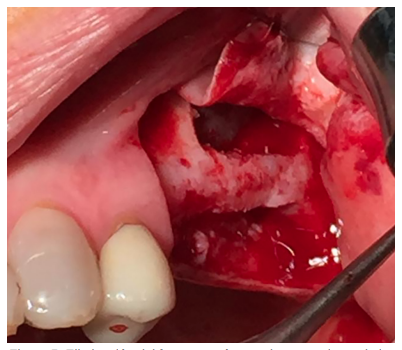

El abordaje quirúrgico fue realizado mediante una incisión lineal crestal y dos descargas verticales, mesial y distal, procediendo al despegamiento mucoperióstico para la obtención de un campo quirúrgico adecuado. Se realizó el diseño de una ventana lateral con piezoeléctrico (VarioSurgery®) (Figura 4), despegándose a continuación la membrana sinusal sin perforación alguna (Figura 5). A continuación, se procedió al relleno mediante un compuesto de fosfato de calcio-potasio-sodio bioactivo (Osseolive®) (Figura 6), acompañado de la colocación de una membrana de ácido poliláctico (EPI-Guide®) (Figuras 7 y 8), finalizando la intervención con la reposición del colgajo mucoperióstico y sutura con poliamida de 4/0 (Supramid®) (Figura 9).